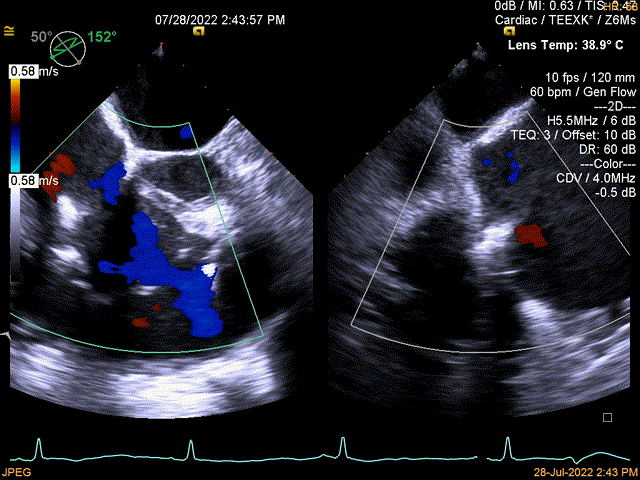

图3:术后即刻TEE

同时其夹子系统继承于申淇淇麟®-经导管二尖瓣夹及可操控导引导管系统优秀设计,具备四个不同型号的夹子及瓣叶分开捕获能力,从而适用于更加复杂多变的三尖瓣解剖。因该患者三尖瓣反流束较宽,瓣叶存在较宽的关闭裂隙,术中很好的利用了瓣叶分开捕获的功能,于后隔瓣区域行瓣膜缘对缘修复。植入一枚长宽夹子后,术后即刻患者反流直接从5级减到2级,患者术后回复良好,自觉症状与临床病情明显改善。